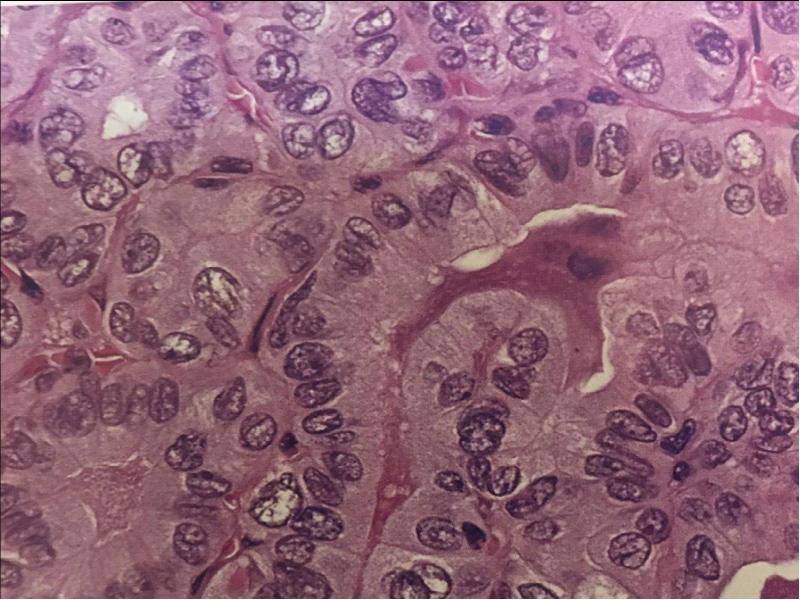

Фотографии опухоли медуллярной аденокарциномы

Раздел: Снимки-откровения